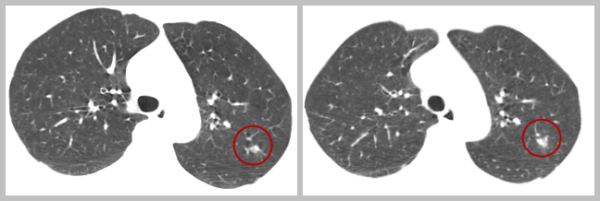

早期肺癌的诊断是近期MDT讨论会上的焦点。一名55岁的女性患者于2019年体检时发现左肺上叶纯磨玻璃结节,今年5月复查肺部CT,姚景江仔细对比两次肺部CT,发现磨玻璃结节较前稍增大,磨玻璃结节内出现部分实性成分,其CT值有所增高,考虑Lung-RADS 4类结节,早期肺癌可能性大。姚景江建议患者进行外科干预,病灶靠近肺外周可以考虑肺段楔形切除,MDT其他成员经过一番讨论后表示支持他的结论,后来患者在本院胸外科做了手术,手术后病理结果证实为贴壁型浸润性肺腺癌。

2019-9-15 2022-5-8

姚景江表示,随着CT技术的发展,CT应用于早期肺癌筛查可清楚地看到人体肺部的结节,早期恶性病变有迹可循,早期肺癌的检出率提高。这样一来,早期肺癌患者获得了早治疗的机会,可通过手术治疗去除隐患,不给潜在的癌变组织以发展成为威胁生命的严重癌症的机会,从而获得长期生存。